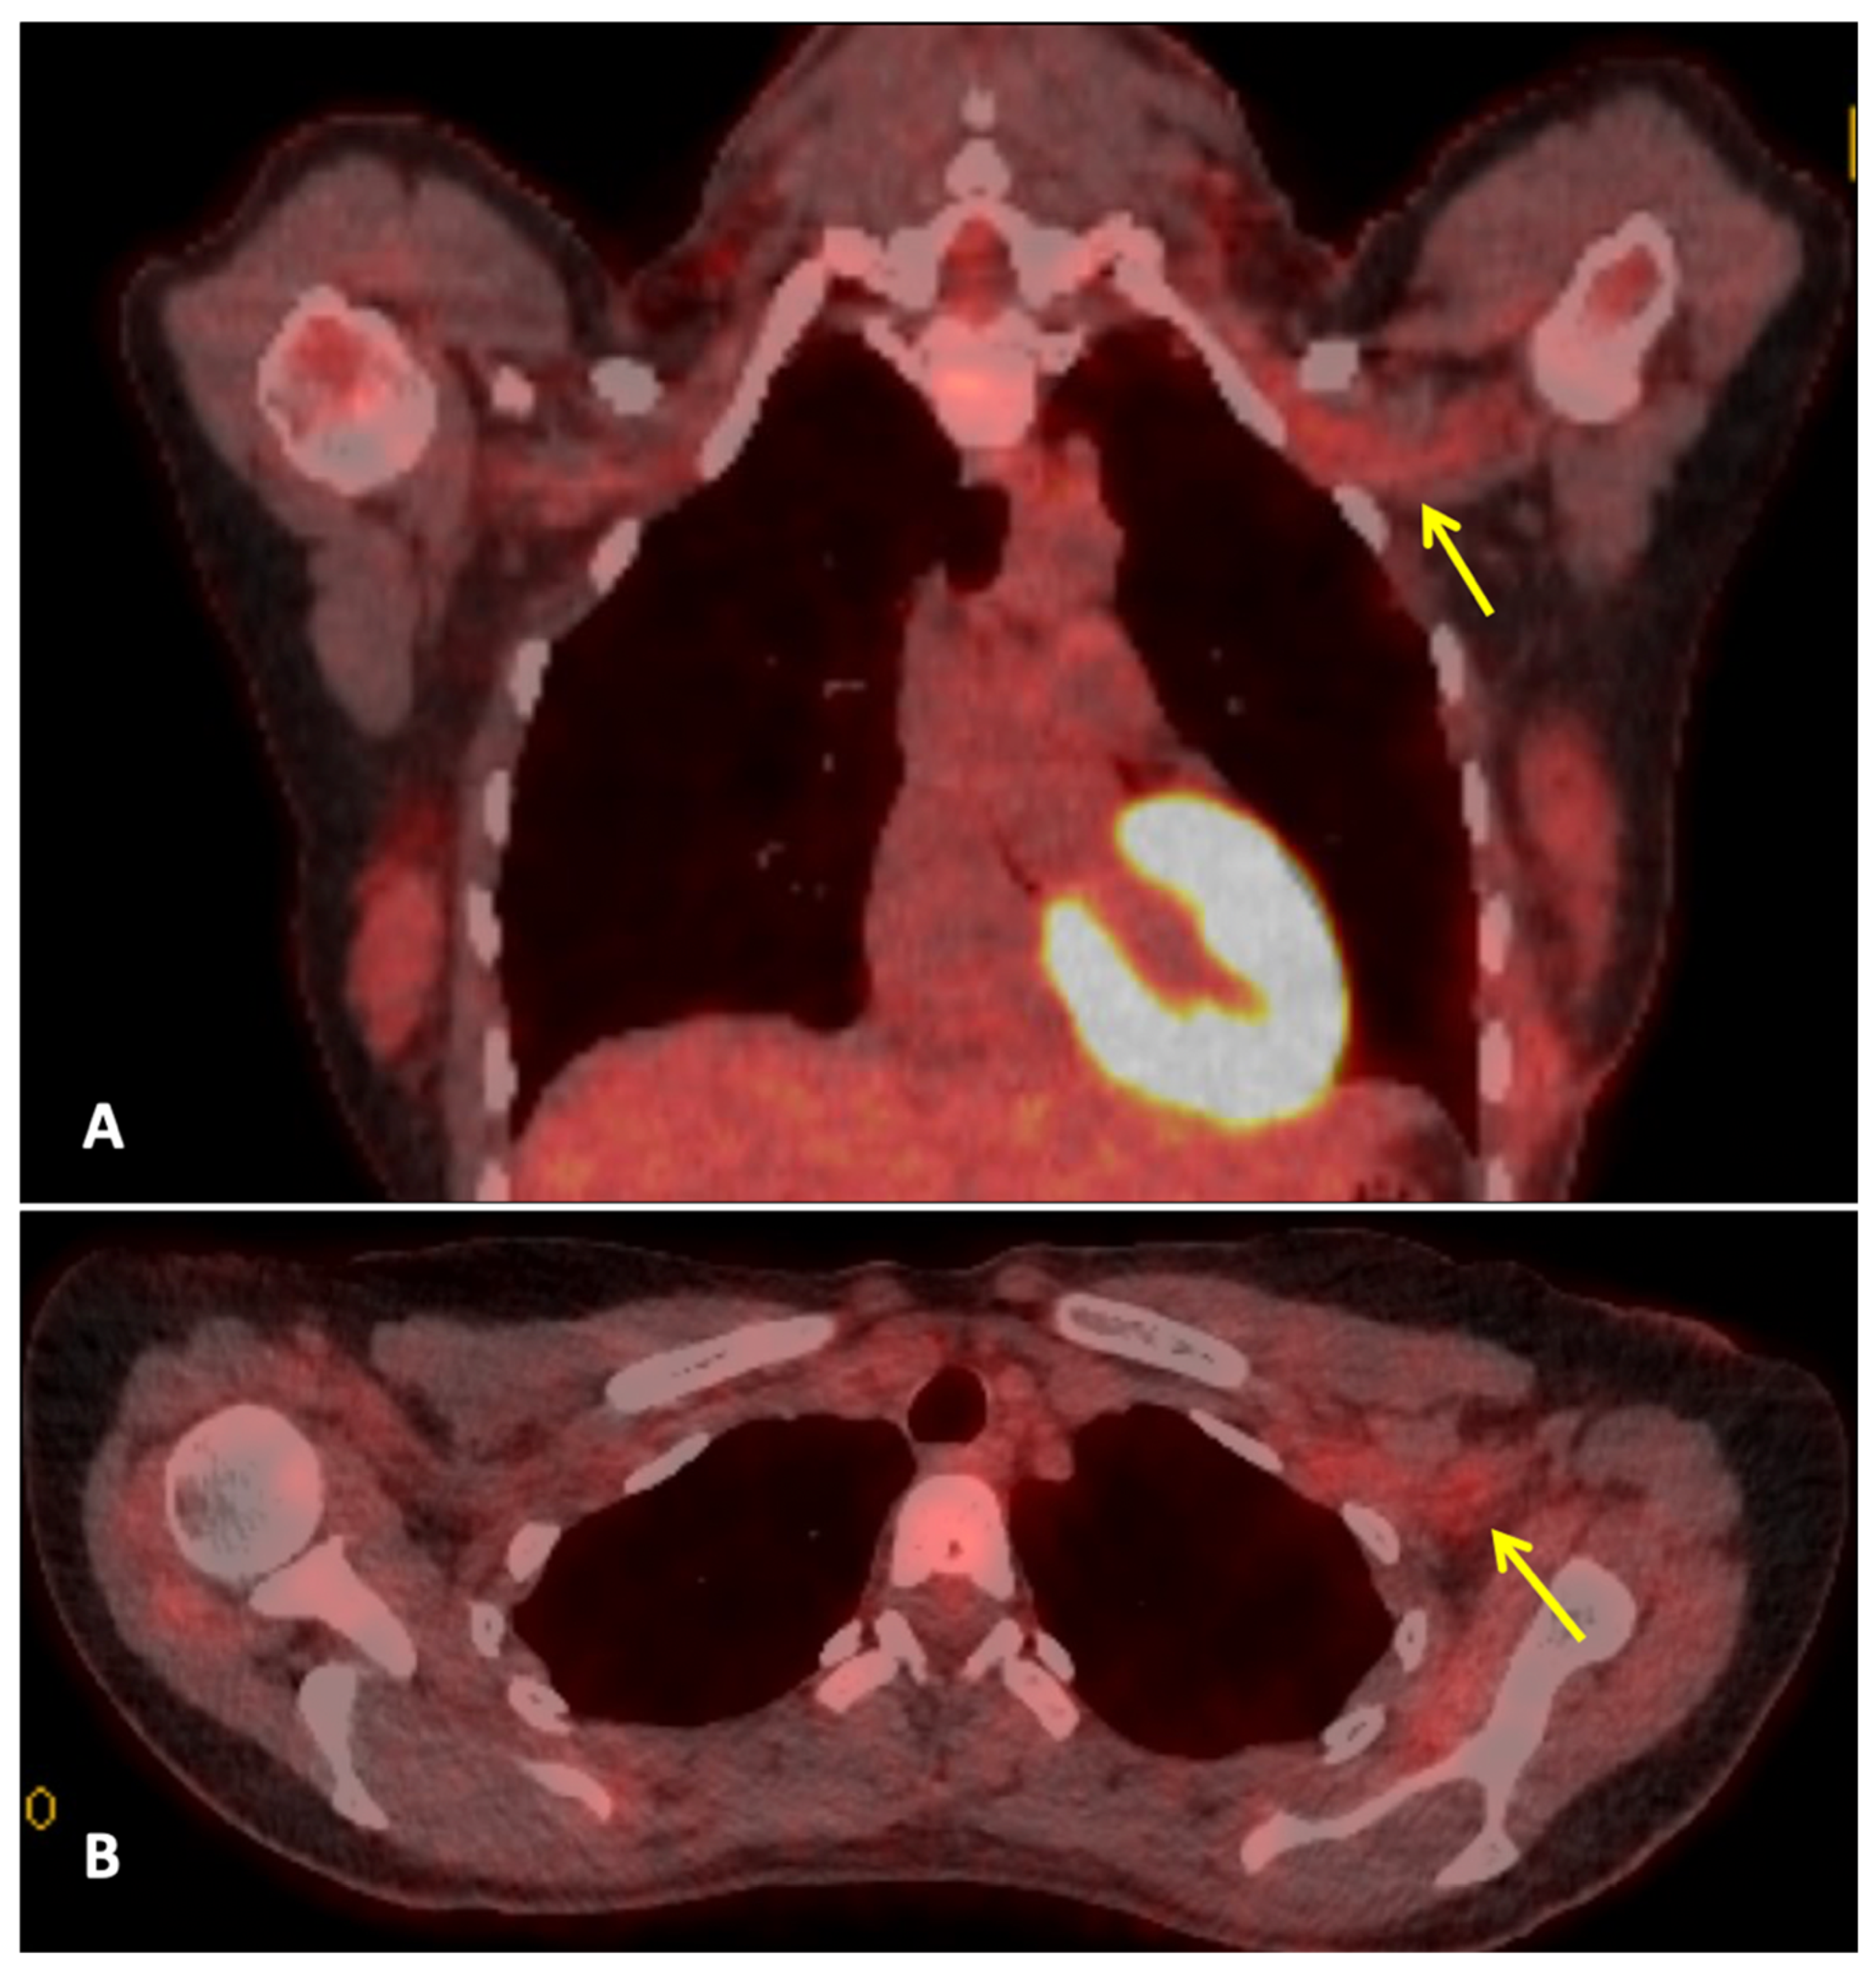

Three months after completing radiotherapy, she developed progressive numbness, paraesthesia, and weakness of the left hand. Examination revealed wasting of the thenar and hypothenar eminences, reduced grip strength, and patchy sensory loss in a C8/T1 distribution. Due to residual cancer burden after surgery, a local recurrence was initially suspected. MRI of the cervical spine and brachial plexus (Figure 1) did not demonstrate metastatic disease, but findings were consistent with brachial plexitis. No recurrent disease was identified on PET-CT, but asymmetric low-grade uptake in the left brachial plexus was also consistent with brachial plexitis (Figure 2), confirming the absence of malignancy. Electromyography (EMG) (Table 1 and Table 2) and nerve conduction studies demonstrated denervation consistent with a lower-trunk brachial plexopathy; onconeuronal antibody serologies were negative.

Figure 2.

Whole body FDG PET-CT: This is a figure. Images (A,B) are coronal and axial fused PET-CT images of the thorax. They demonstrate asymmetric low-grade uptake in the left brachial plexus (yellow arrows) compared to the right side, but there is no soft tissue mass or high-grade uptake to suggest metastatic disease.

In this patient, the presentation of progressing ipsilateral upper limb neurological symptoms (numbness, paraesthesia, and hand weakness) suggested locoregional recurrence, especially given her incomplete pathological response. These symptoms usually point towards locoregional recurrence, radiation-induced brachial plexopathy (RIBP), or metastatic disease. It further required ample imaging and neurophysiological evaluation [18,19,20]. MRI and PET-CT, however, demonstrated no evidence of tumour recurrence, nodal disease, or infiltrative pathology. MRI is integral in differentiating tumour infiltration, radiation-induced fibrosis, and inflammatory plexopathies. The absence of mass effect or structural abnormality in this case reduced the possibility of a malignant or compressive cause. However, electromyography revealed findings consistent with lower trunk brachial plexopathy [18,21].